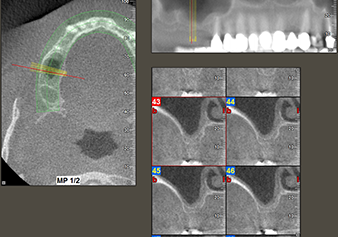

Une patiente de 49 ans, non fumeuse et sans antécédents médicaux remarquables, a été orientée vers notre cabinet de chirurgie orale pour l’extraction chirurgicale de la dent 16 préalable à la pose d’un implant. Après l’extraction, la patiente a rencontré de légers problèmes de sinusite, à la suite de quoi nous avons commencé par attendre six mois avant de prendre la mesure. À l’endroit prévu pour la pose de l’implant, l’os résiduel mesurait 3-4 mm de haut (Fig. 1 et 2).